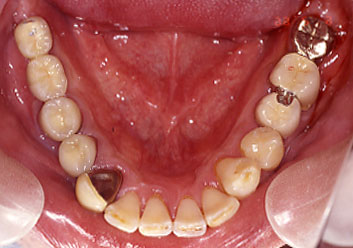

左下第一大臼歯の遠心根と第二大臼歯の近心根を分割抜歯し、舌側に転位していた左下5を歯列内に戻してブリッジを作製しました。

初診時にかぶせたブリッジの5年後の状態。右下大臼歯はインプラント。

上図は部分的な矯正治療により、むし歯や根の病気が進んだ大臼歯を移動し、ブリッジとして保存したケースですが、9年後同部の歯槽骨はかなり吸収が進み、結局インプラントによる再治療を必要としています。

同じ患者さんの反対側の欠損部には、早期にインプラントが埋入された結果、歯槽骨吸収は抑制され、良好な咀嚼機能が温存されていることを考えると、例え、一時的には高額な治療費を必要としても思い切ってインプラントによる確定的な治療をなるべく早く行ってしまったほうが、総合的に見て患者さんのためになるのではないかとも考えられます。

左下大臼歯部の歯槽骨はかなり吸収が激しく、インプラント手術もかなりむつかしいケースになってしましました。

今から思えば、右下大臼歯にインプラントを埋入したのに、なぜ左下大臼歯部も早期に抜歯してインプラントを埋入することを患者さんに勧めなかったのか悔やまれる症例です。